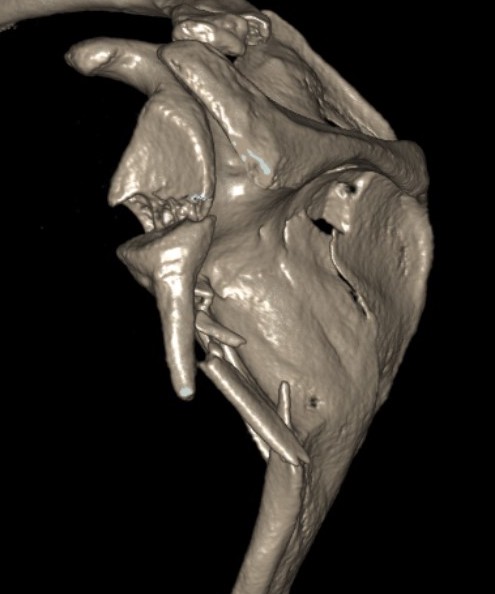

Combined scapula body fracture / intra-articular glenoid fracture